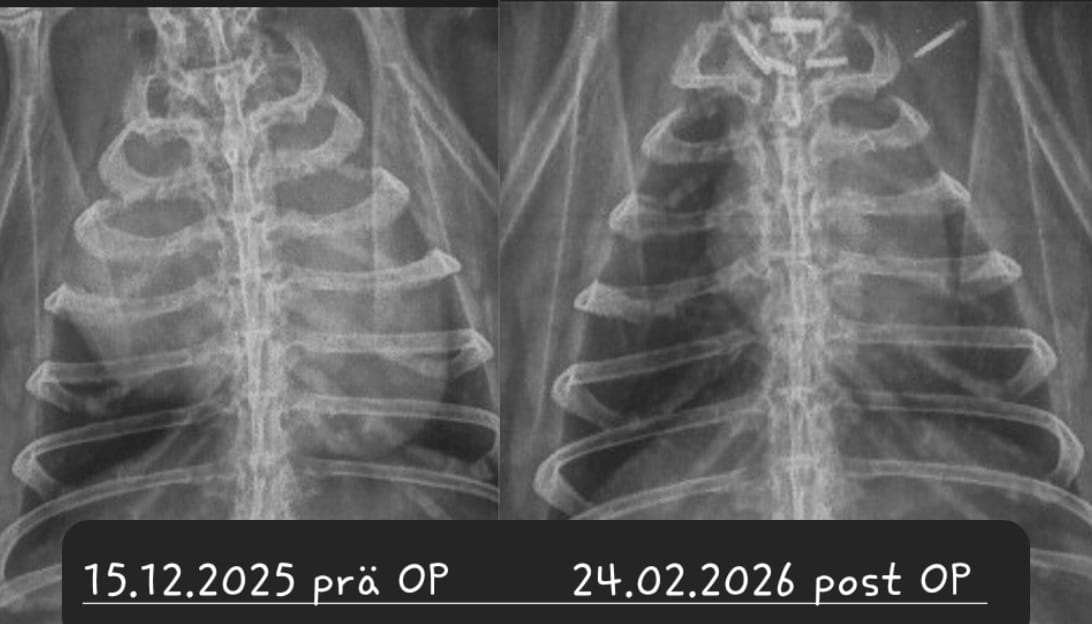

Ein Kaninchen mit Atembeschwerden oder den beschriebenen Augenveränderungen sollte zunächst geröngt werden. Hierdurch lassen sich Verschattungen im Brustkorb schnell und einfach erkennen und es muss anschließend nur noch ermittelt werden, ob es sich dabei um einen Tumor oder eine (reine) Herzerkrankung handelt. Letztere kann zu einem vergrößerten Herzen oder einem Erguss führen, was per Röntgendiagnostik nicht immer von einem Tumor zu unterscheiden ist.

Bei einer Thymom- oder Lymphom-OP handelt sich um einen schwerwiegenden Eingriff, bei dem der Brustkorb des Patienten eröffnet wird und der Tumor möglichst vollständig entfernt werden muss, ohne dabei das benachbarte Herz zu schädigen. Die OP wird nur von wenigen Chirurgen angeboten. Ein Spezialist, der regelmäßig auch Patienten aus Deutschland operiert, ist Dr. Florent Modesto in Brüssel.

Sofern davon auszugehen ist, dass das Kaninchen den Eingriff übersteht und der Tumor sich vollständig entfernen lässt, ist die OP zwar die kostspieligste, aber vermutlich auch die Option mit der besten Prognose

Leider ist trotz allem damit zu rechnen, dass Zellreste des Tumors zurückbleiben und nach einiger Zeit nachwachsen. Je nach Tumor-Art ist dies allerdings mitunter erst nach 3-5 Jahren der Fall - womit das Kaninchen sehr viel Lebenszeit gewonnen hat; hinzu kommt die verbesserte Lebensqualität, nachdem die Masse aus dem Brustkorb entfernt wurde und langfristig auch keine Medikamente gegeben werden müssen.